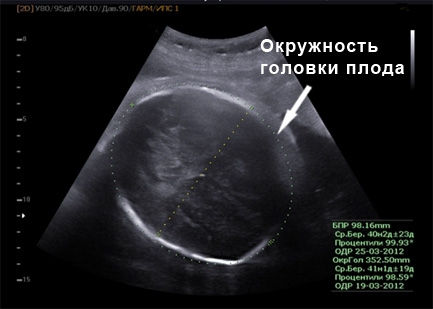

УЗИ на 40 неделе беременности

Ультразвуковое исследование на 40-й неделе беременности проводится исключительно при наличии определенных показаний. В этот период толщина плаценты составляет 33-34 см, а ее зрелость, как правило, определяется как третья степень. Во время родов ультразвук не используется, и состояние малыша контролируется с помощью датчиков сердечного ритма.

Фото УЗИ на 40 неделе беременности

На 40-й неделе беременности масса плода составляет примерно от 3,5 до 4 кг. Размеры головы достигают 93,8 мм, грудной клетки – 98,6 мм, а окружности живота – 103,4 мм. Ожидаемый рост плода составляет около 50-54 см.